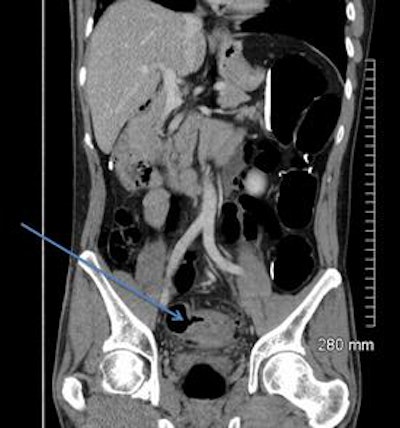

A 52-year-old man with a benign stricture, categorized as C4E1D4. The arrows highlight the smooth gradual transmural thickening within a diverticular laden sigmoid colon. Benign stricture was confirmed with surgical resection.

In terms of pathology within the D3 and D4 categories, 60 cases showed sigmoid diverticular disease on imaging, 10 showed sigmoid strictures, diverticular abscesses were found in five cases, and two cases included Crohn's or ulcerative colitis, they reported. Within the D3/D4 category, 24% underwent further intervention, either surgical (eight cases) or endoscopic (12 cases).